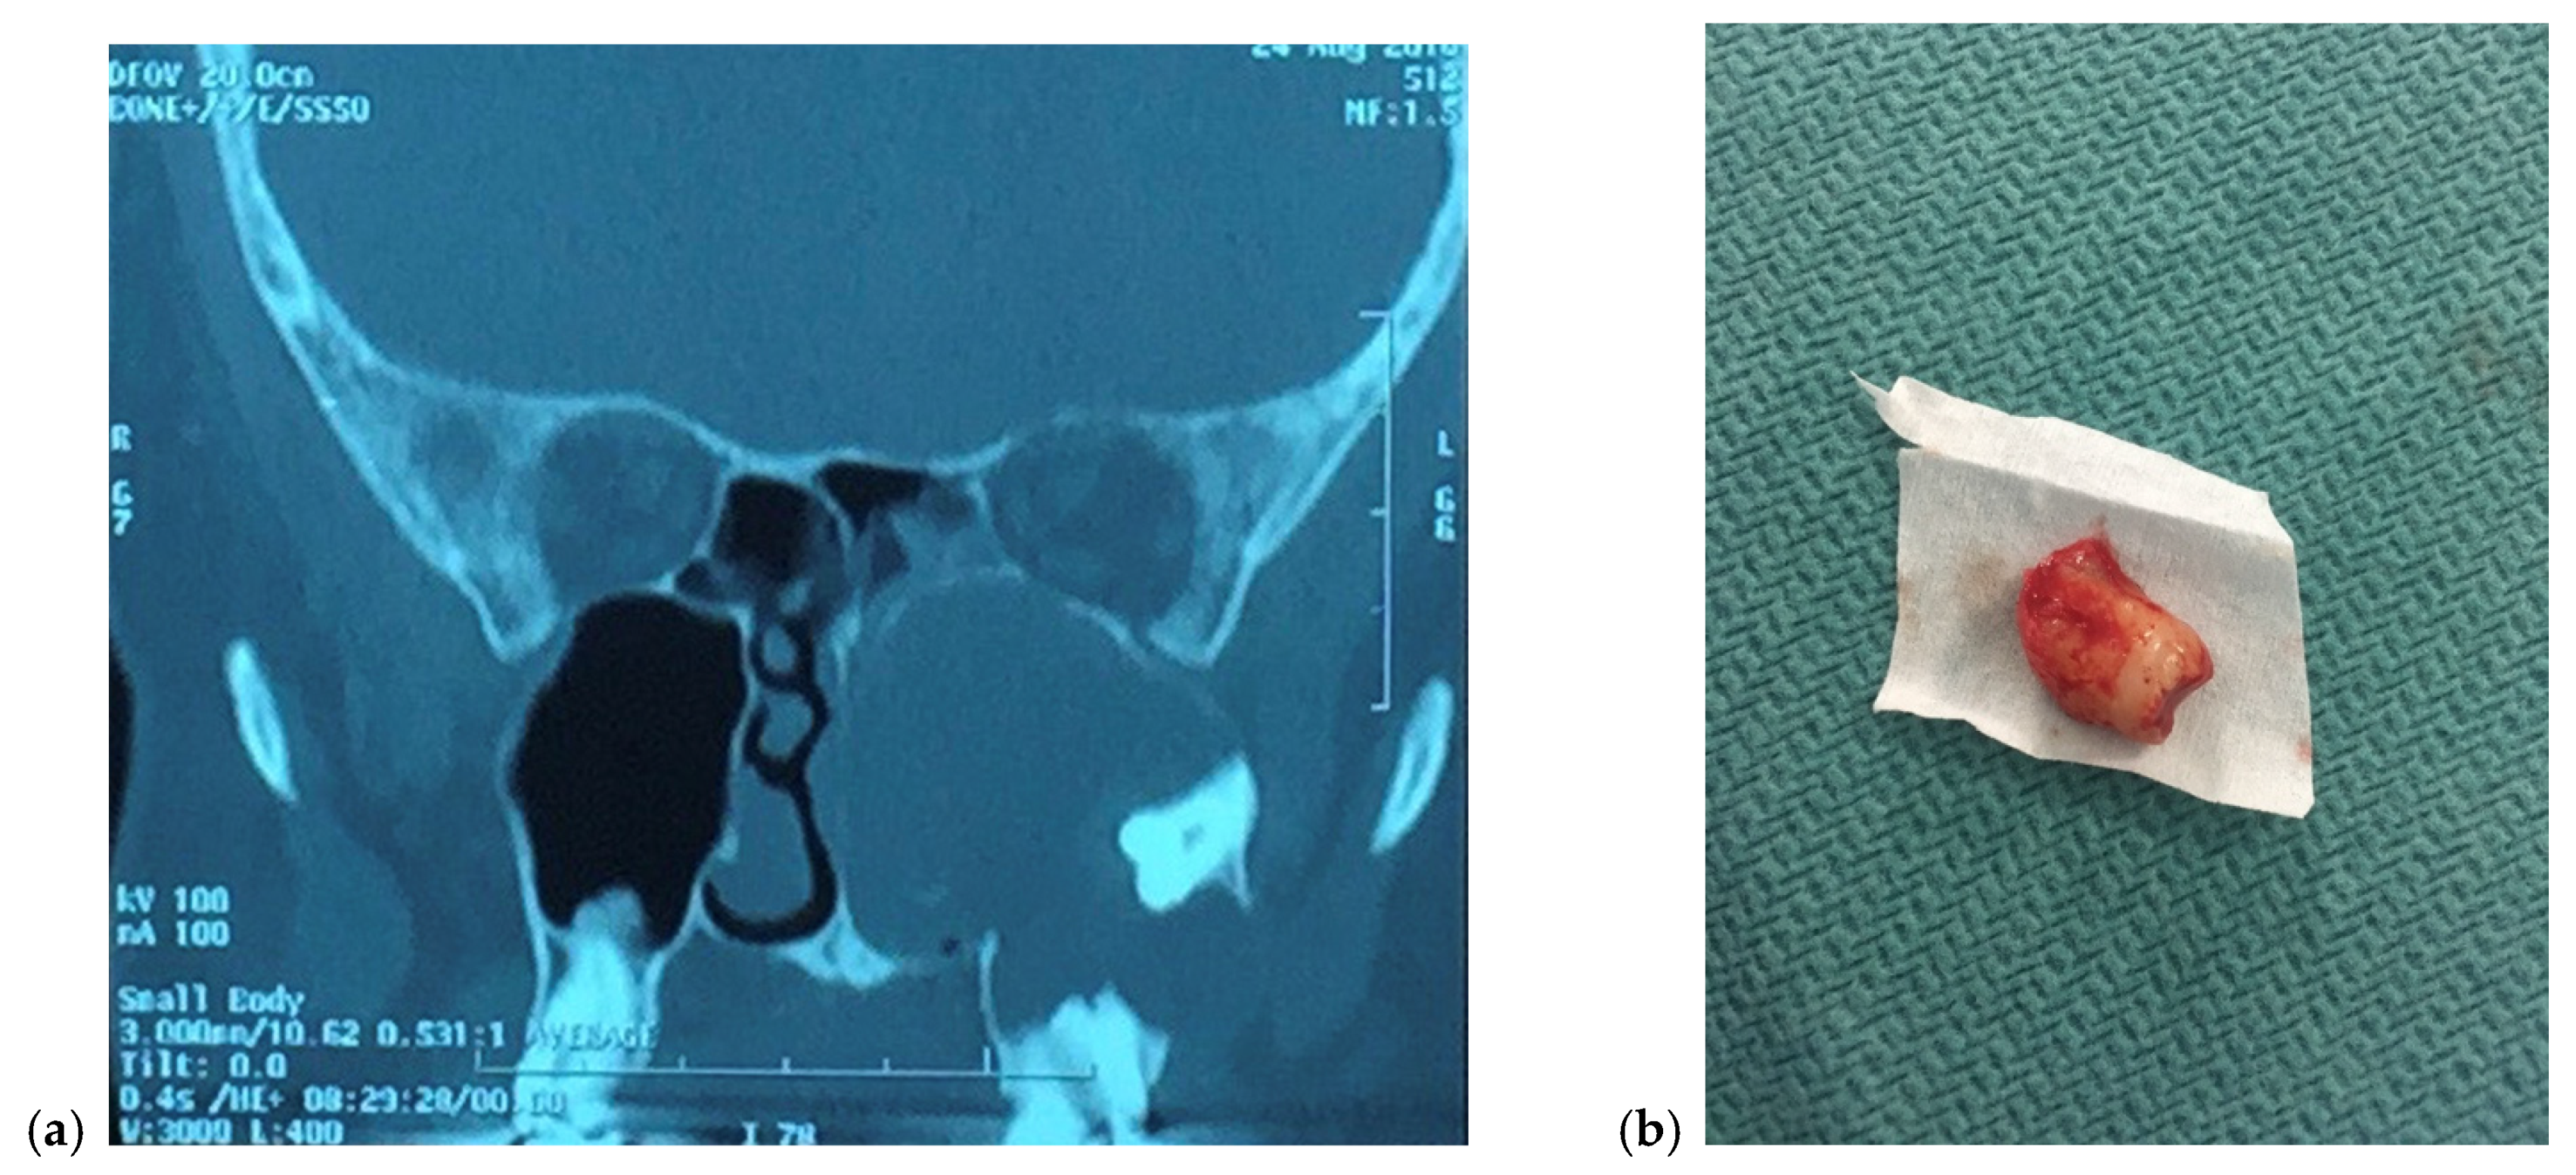

2.1. Iatrogenic